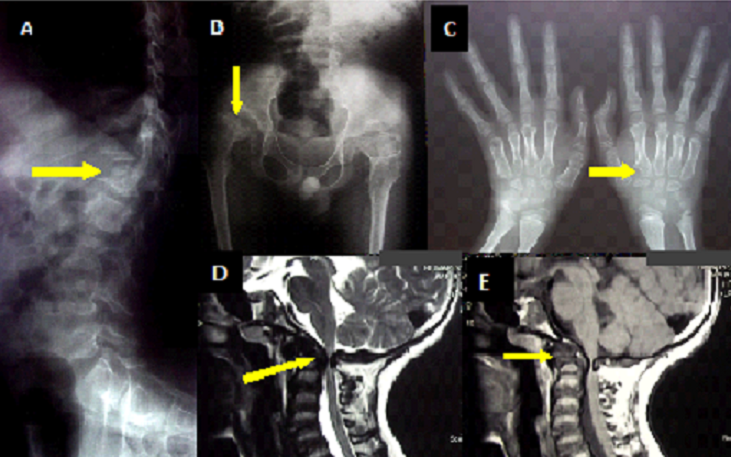

A 12 years old boy, with no past medical history, presented to the neurology department with a 7 years clinical course of untreated limping, progressive kyphosis, repeated shoulder dislocation, and, recently, progressive limbs weakness. On examination, the patient was short trunked with fixed cervical hyperextension and thoracolumbar kyphosis. Also noted were genu valgum and ligamentous laxity. Neurological examination showed a spastic quadriparesis (3/5), exaggerated reflexes and bilateral Babinsky sign. Sensory function was normal, so as intelligence. Axial and appendicular X-ray radiographs demonstrated odontoid hypoplasia and possible occipito-cervical dislocation, a platyspondyly (image A, arrow), acetabular dysplasia (image B, arrow) and metacarpal irregular proximal ends (image C, arrow). MRI of the craniocervical junction revealed severe spinal cord compression at C1-C2 level with marked instability and dislocation (image D, arrow), odontoid hypoplasia associated with a soft tissue mass around (image E, arrow). All were suggestive of the mucopolysaccharidosesÂ’ origin. Laboratory investigations showed an over excretion of the keratane sulfate which comforted the diagnosis. The differential diagnosis of the image can be made with the atlanto-axial subluxation in rheumatoid arthritis, ankylosing spondylitis, and pseudo-gout (CPPD). The patient was proposed for a cervical posterior decompression with occiput-to C2 fusion, which was declined by his family when surgical procedure risks were explained.